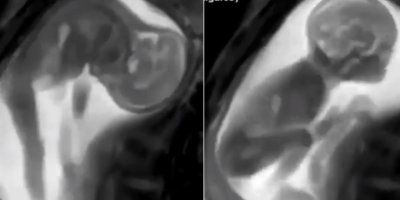

Znanstvenici su proizveli revolucionarne 3D snimke srca bebe u majčinoj utrobi. To bi otkriće moglo pomoći u liječenju beba s prirođenim srčanim manama.

Nerođena beba proteže se, isteže ručice i nožice, katkada reagira na vanjske zvukove ili majčine osjećaje.